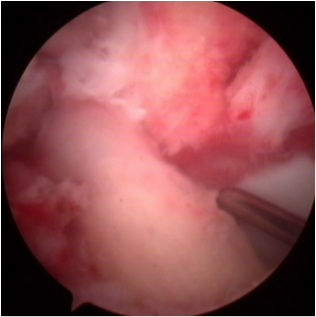

前十字靭帯が断裂している